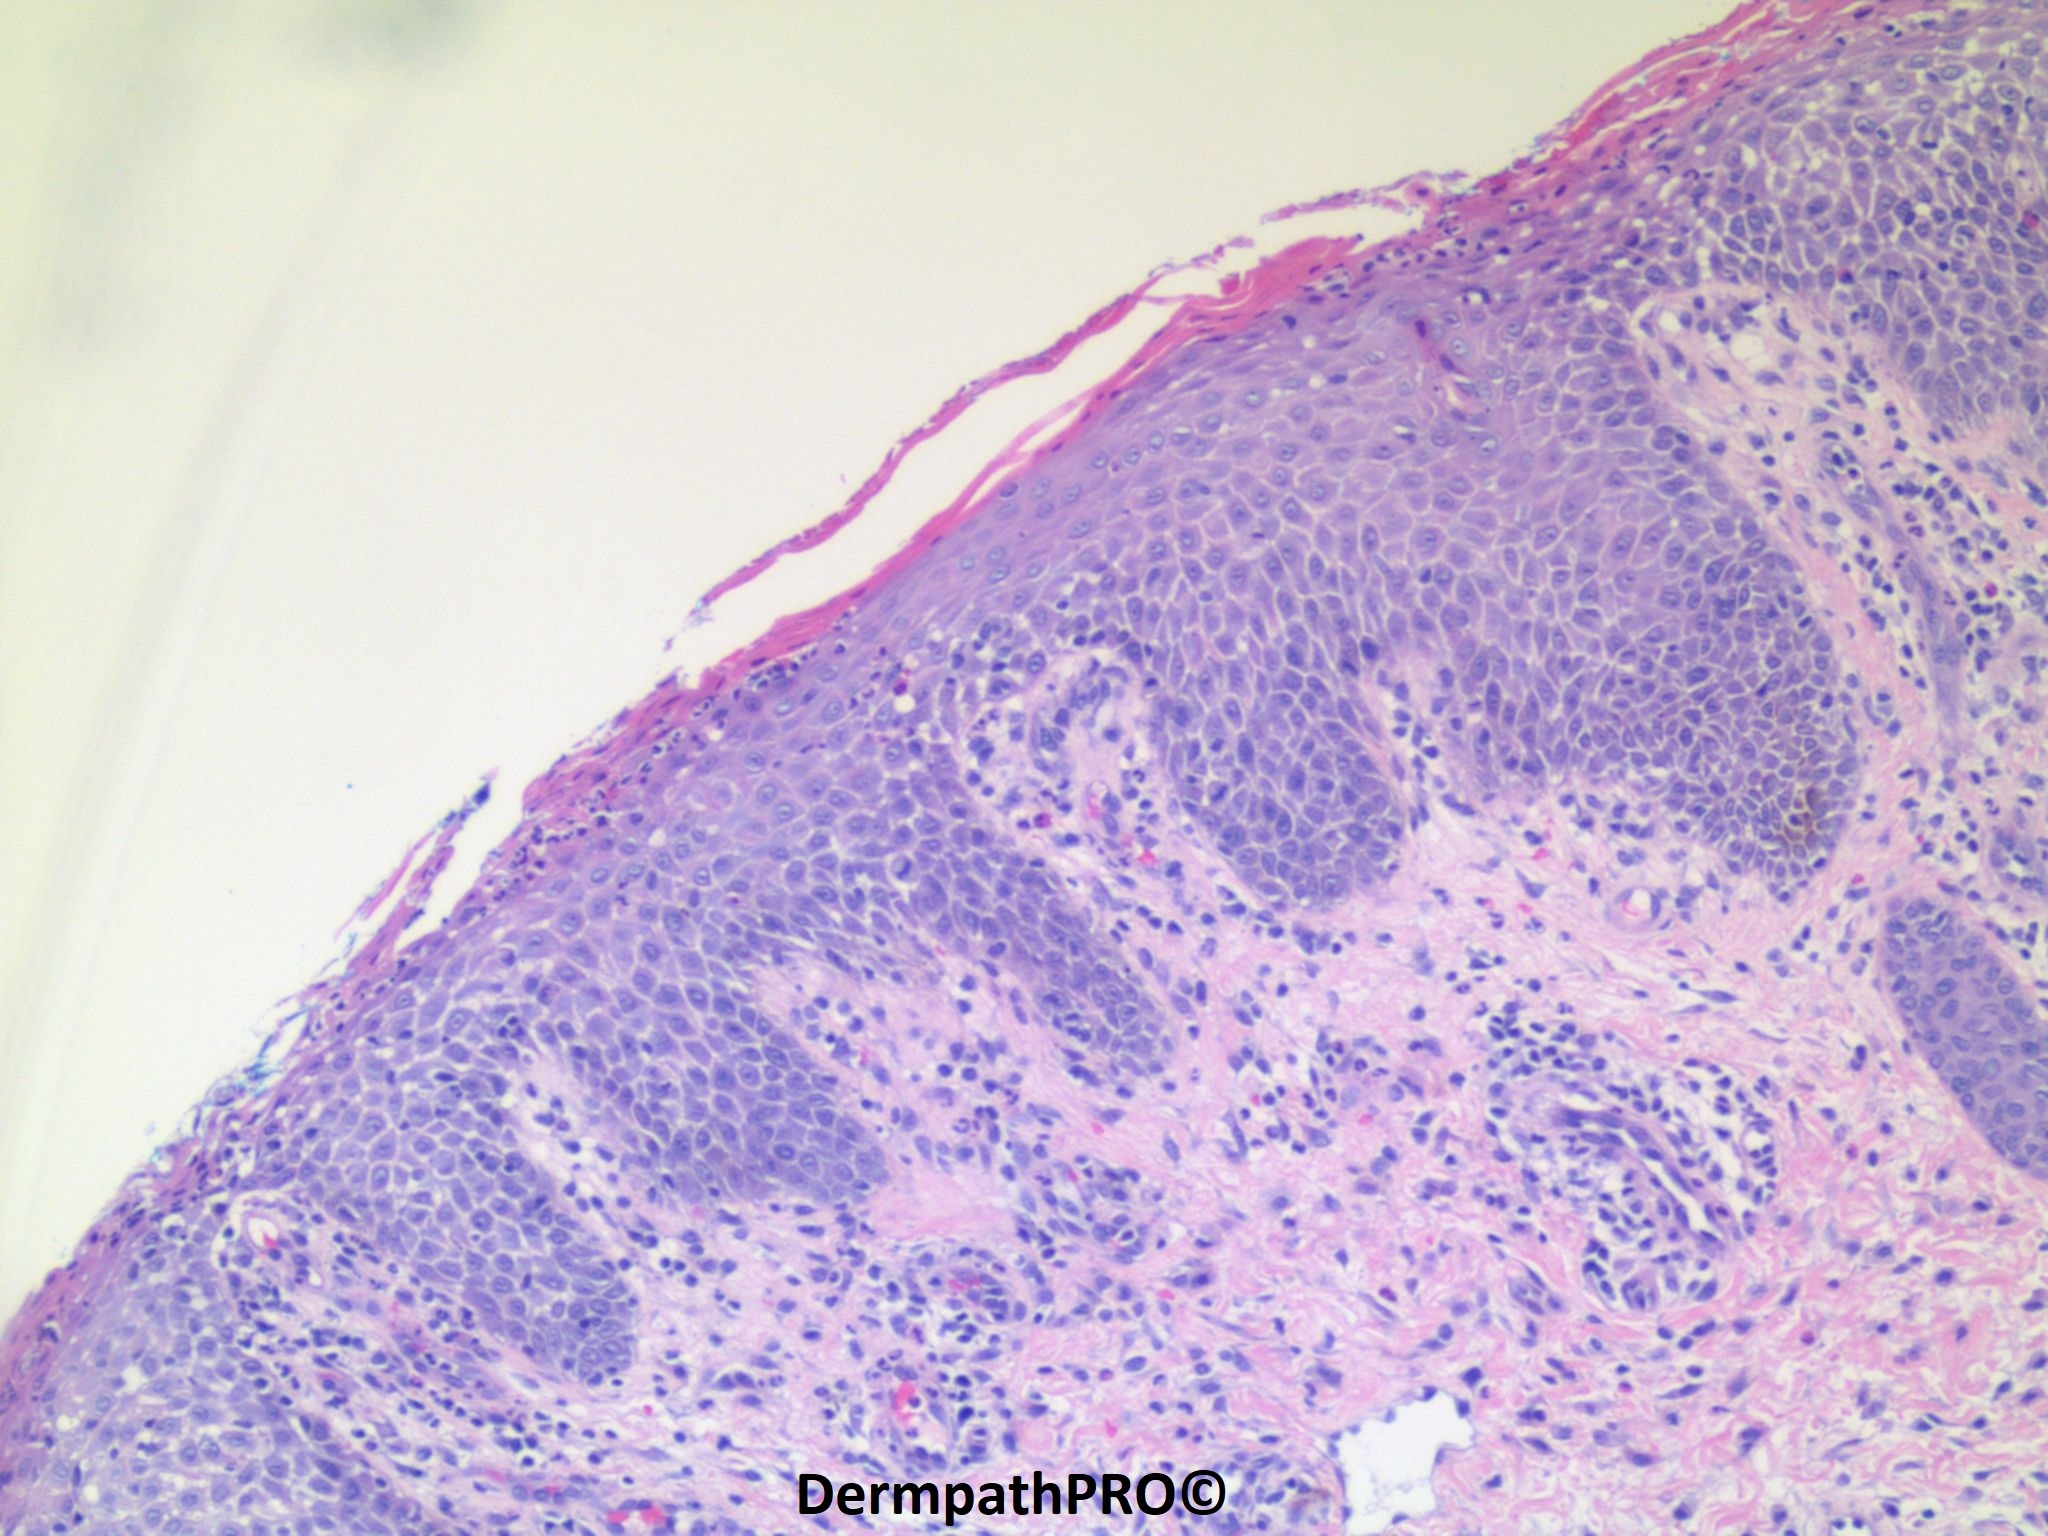

20-year-old Arabic male with history of "eczema". Used oral steroids and topical. Stopped after 2 to 3 days with reflare with total body erythroderma. Exfoliative.

Subcorneal pustules with eosinophils was the final diagnosis. We reviewed the patient's clinical photographs and spoke with the clinician. Our differential diagnosis included: an erythrodermic version of a spongiotic dermatitis, such as atopic dermatitis, contact dermatitis, or drug hypersensitivity reaction; an unusual presentation of acute generalized exanthematous pustulosis (AGEP); a subtle presentation of a primary autoimmune blistering disease (i.e., pemphigus foliaceus). Psoriasis and mycosis fungoides were not favored.